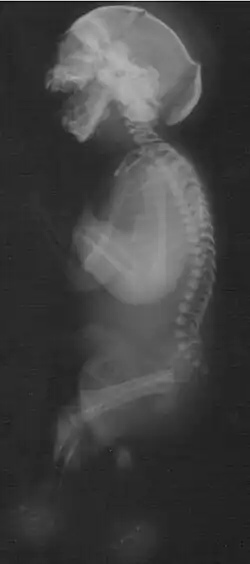

Das Neu-Laxová-Syndrom (auch: Neu-Syndrom, Neu-Povysilová-Syndrom; abgekürzt NLS; engl. Neu-Laxová syndrome) ist ein absolut letal verlaufendes angeborenes Fehlbildungssyndrom, gekennzeichnet durch ein behindertes Wachstum des Fötus und eine Reihe körperlicher Missbildungen.

Zum Krankheitsbild dieser seltenen Erkrankung gehört eine Vielzahl angeborener Fehlbildungen, darunter:

- Fehlbildungen des zentralen Nervensystems:

- Lissenzephalie

- Corpus-callosum-Agenesie

- Mikrogyrie

- Mikrozephalie

- Ödeme der Subkutis

- Ichthyose

- Muskelatrophie

- Fehlstellungen von Fingern und Zehen

- Arthrogryposis multiplex congenita

- Fehlbildungen der Nieren

- Herzfehler

- prominente Fersen

- Syndaktylie der Zehen

- Hypoplasie der äußeren Geschlechtsorgane

- Hypertelorismus

- fehlende Augenlider

- verkürzter Hals